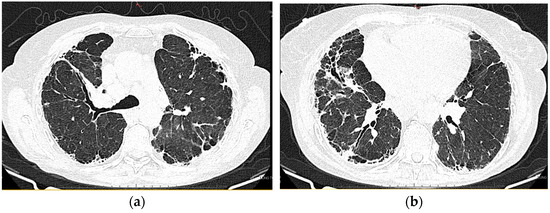

2.1.6. High-Resolution Computed Tomography (12 October 2022) (Figure 2)

Thyroid gland of normal appearance. Advanced fibrotic changes in both lung fields with septal thickening, architectural disorganization, and traction bronchiectasis, with the changes being more important at the basal level of the bilateral lower lobes. Small diffuse calcified granulomas bilaterally, without areas of pulmonary condensation. Absence of suspicious pulmonary nodules. Trachea and bronchi with free lumens. Absence of mediastinal masses. Absence of pleural fluid accumulations. Mediastinal adenopathies up to 17 mm perivascular, 16 mm pretracheal at the right, 18 mm left hilar, 15 mm right hilar, and multiple subcentimeter, some with punctate calcifications. Esophagus minimally dilated with liquid content. Cardiomegaly, pericardial blade up to 18 mm in the right ventricle. Accentuation of dorsal kyphosis. Early degenerative changes in the dorsal spine, without suspicious lesions on the scanned bone segment. Conclusions: Pulmonary fibrosis changes with medium-advanced damage. Pericardial minimum. Esophageal stasis, more likely in the context of achalasia. Bilateral mediastinal and hilar adenopathies, some with calcifications.

2.1.10. High-Resolution Computed Tomography (March First 2023) (Figure 3)

Predominantly subpleural reticular lesions, with a four-cornered appearance, associated with minimal right anterobasal peribronchovascular extension. Traction bronchiectasis is associated with the reticular beaches above. Subpleural areas of honeycombing are more accentuated in the lower half of the lung. Discrete peripheral organizing masses, especially in the left posterior. Fibrous bands with small associated calcifications. The pleural contour is irregularly marked, with numerous spicules on the contour. The esophagus is markedly dilated along its entire length, with a caliber of up to 26 mm, regular walls, and liquid stasis in the lower half. Circumferential pericarditis in a small amount. Global cardiomegaly. The pulmonary artery cone has a caliber of 36 mm, in the context of known pulmonary hypertension. Numerous supracarinal bilateral mediastino-hilar adenopathies, some of them with small calcifications, with an inflammatory appearance. Thyroid with normal position and dimensions, inhomogeneous, micropolynodular structure. Conclusions: The CT appearance is an appearance of interstitial lung pneumopathy: progressive fibrosing phenotype, examination quasi-identical to the previous CT examination. Dilated pulmonary arteries with the appearance of PAH. Minimal pericarditis. Cardiomegaly. Polynodular goiter. Dorsal spondylarthrosis.

Considering the underlying pathology, progressive systemic sclerosis and interstitial lung disease, the next step in the diagnostic process was progressive evaluation. The restrictive pattern expressed on the body plethysmography associated with a significant decrease in DLCO, the clinical deterioration of the patient, and the progression of imaging lesions on HRCT led to the classification of the patient as having an SSC-ILD progressive phenotype.